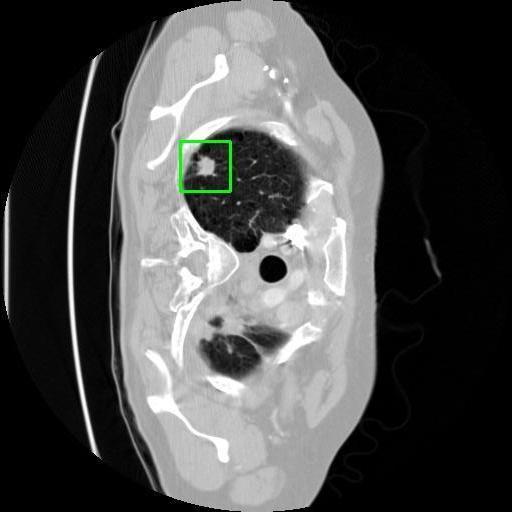

We developed an AI-based system using deep learning models for analyzing lung CT scans to detect and classify pulmonary nodules. We chose the YOLOv11 architecture for its enhanced object detection capability and adapted it specifically for medical imaging, incorporating pixel-level precision and severity classification.

Classification into three severity levels with colored bounding boxes.

Successfully built and deployed an AI model (YOLOv11) capable of detecting lung nodules in CT scans with high accuracy and real-time performance.

Designed a severity classification system that categorizes nodules into null, moderate, and severe using colored bounding boxes, assisting in rapid clinical decision-making.